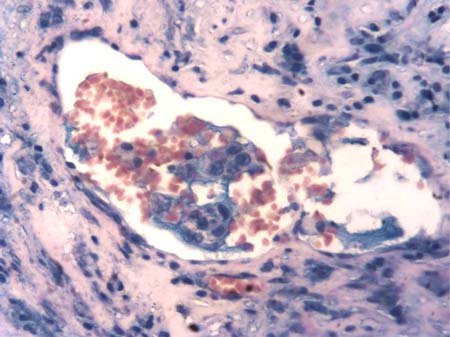

В результате изготовления серийных срезов с реакцией МКАТ против пан-цитокератинов был выявлен 551 непоражённый ЛУ, 38 — с наличием изолированных клеток опухоли или их кластеров (рис. 1), 122 — с микрометастазами (рис. 2), 479 — с метастазами различного объёма и 73 ЛУ, полностью замещённых опухолевой тканью. В двух последних случаях метастазы хорошо определялись и без иммуногистохимического исследования. Сеть кровеносного микроциркуляторного русла ЛУ выявлялась по экспрессии МКАТ против CD31 в эндотелии и против коллагена IV типа в базальных мембранах сосудов (рис. 3).

Рис. 2. Микрометастаз в субкапсулярном синусе. Реакция с моноклональными антителами против пан-цитокератинов. LSAB-метод с докраской гематоксилином. ×400